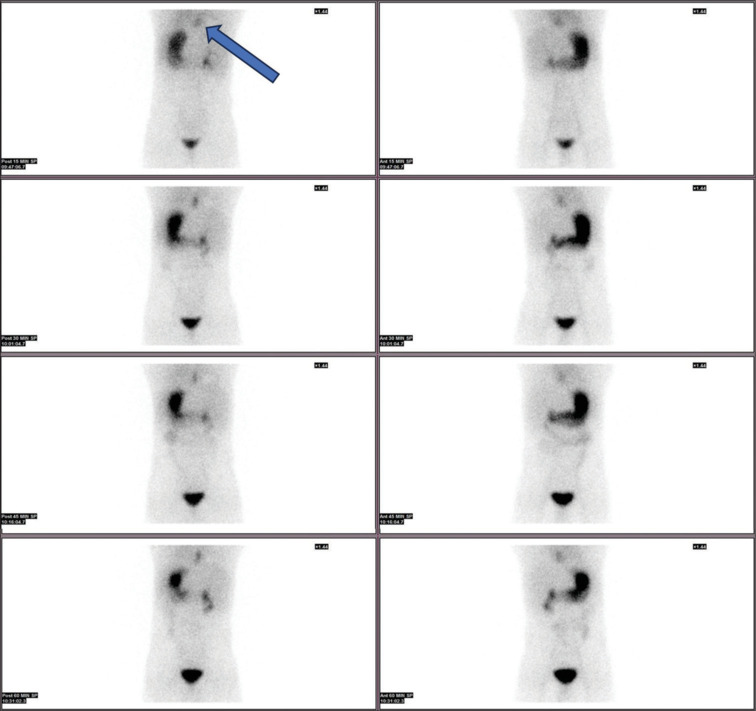

Enteric duplications are rare congenital anomalies, which can have varying presentations depending on the size, location, and type of mucosa present. Meckel scan, using technetium-99m pertechnetate (Tc-99m pertechnetate), is a useful modality for the detection of ectopic functioning gastric mucosa. Thoracic duplication cysts present as the initial photopenic area which is getting filled by Tc-99m pertechnetate in the delayed static images of Meckel scan. We report a rare case of foregut duplication cyst, where foregut duplication cyst is visualized earlier in Meckel scan.